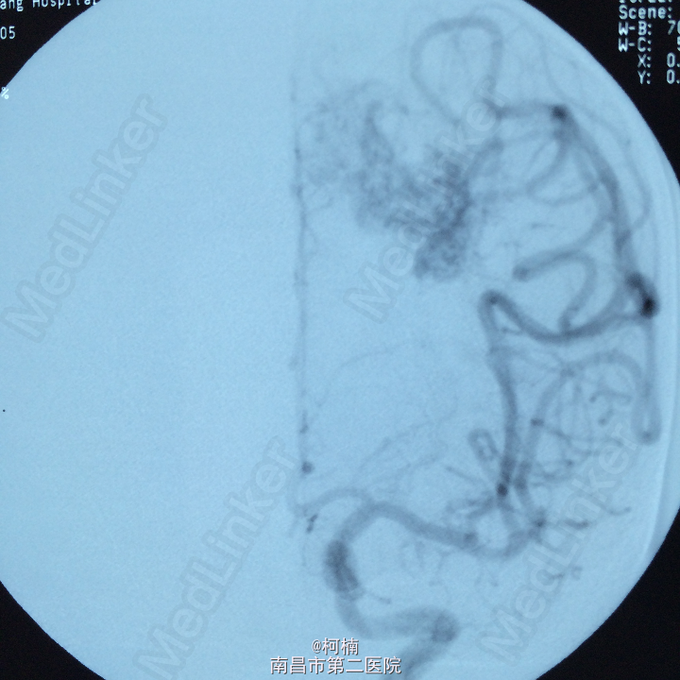

诊断:脑动静脉畸形 处理:予急诊行DSA检查,提示脑动静脉畸形,予行血管内栓栓塞治疗